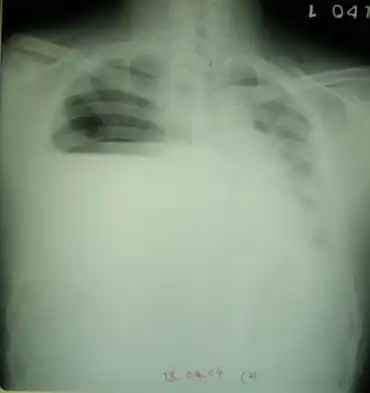

| Arcanobacterium haemolyticum associated with pyothorax-Clinical examination and imaging studies revealed a right sided multi-loculated hydropneumothorax | |